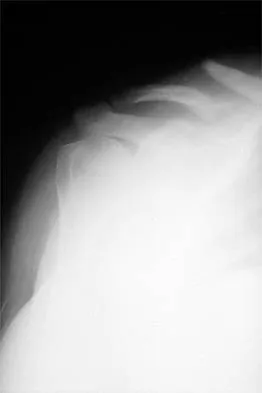

Figure 17 shows the radiograph of a 25-year-old professional football player who has superior shoulder pain that prevents him from sports participation. History reveals that he sustained a shoulder injury that was treated with closed reduction and temporary pinning 3 years ago. The best course of action should be

Explanation